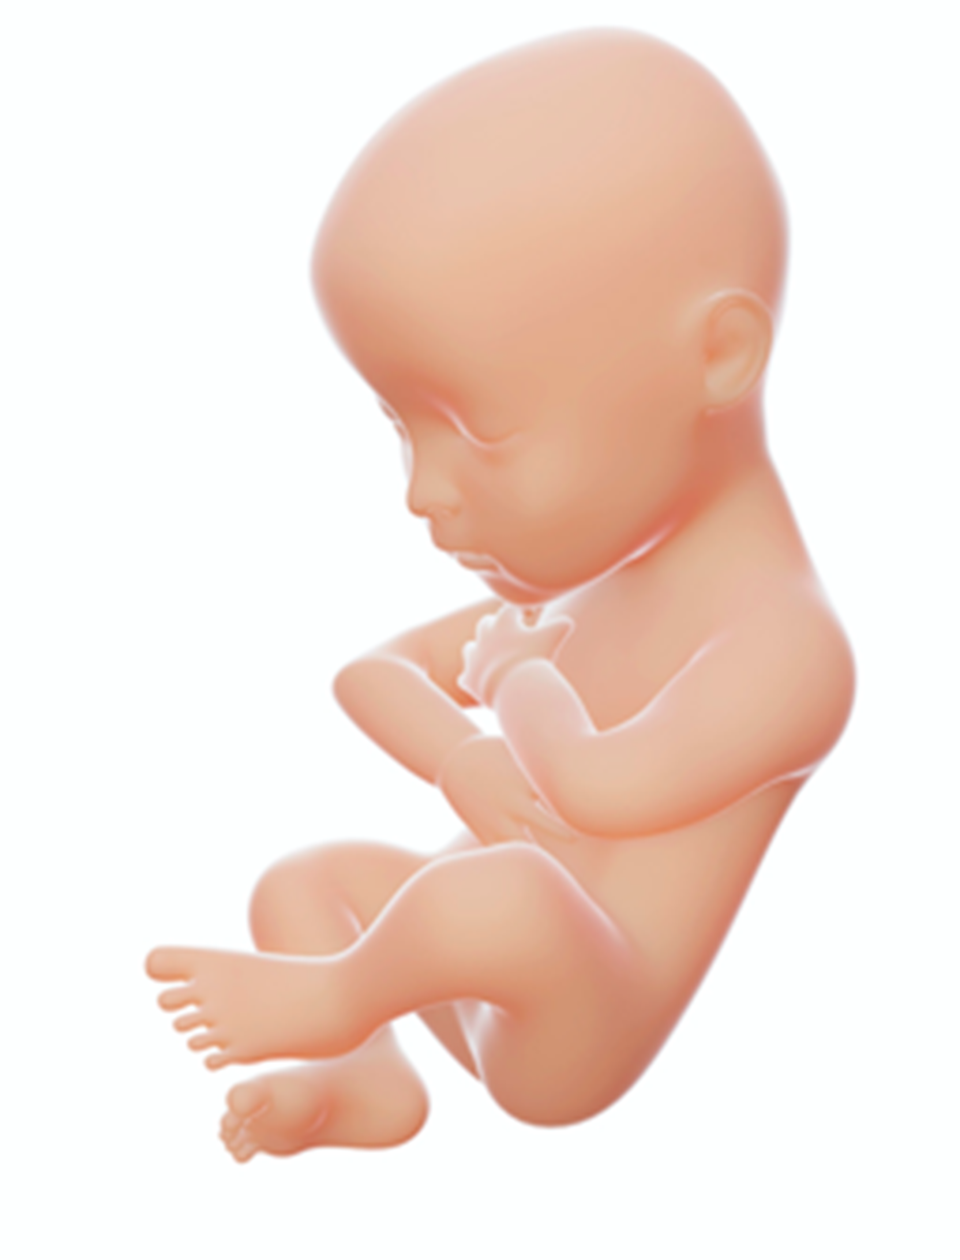

III trymestr | 7 miesiąc | 40–45 cm | Kształty płodu zaokrąglają się. Zachodzi intensywny rozwój mózgu. ![]() Źródło: Englishsquare.pl Sp. z o. o., licencja: CC BY-SA 3.0. |